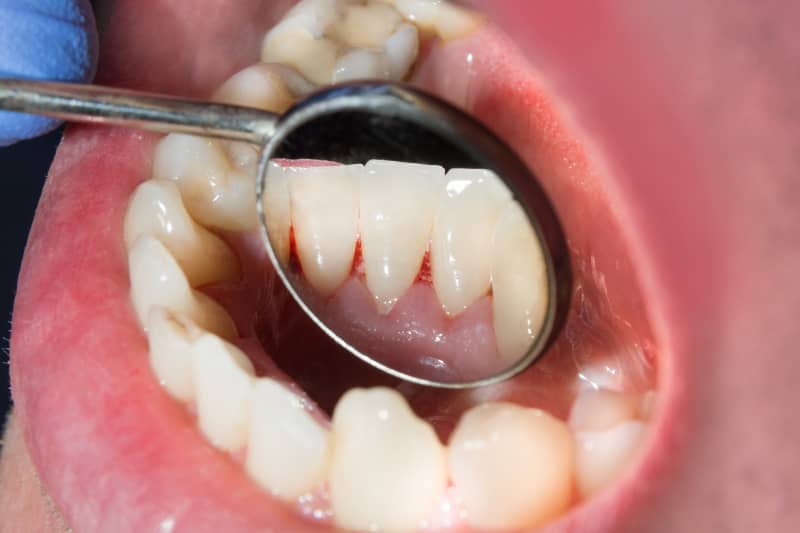

Sanfte Hilfe bei Zahnfleischentzündung, Zahnfleischrückgang und Zahnfleischbluten

Parodontitis – im Volksmund oft als Parodontose bekannt – ist eine weit verbreitete Erkrankung, von der über die Hälfte der Erwachsenen betroffen ist, häufig ohne es zunächst zu bemerken. Was harmlos mit Zahnfleischbluten oder Mundgeruch beginnt, kann unbehandelt zu einer bakteriellen Entzündung des Zahnraums führen, den Kieferknochen schädigen und sogar Zahnverlust verursachen. Doch keine Sorge: Bei DentalGut in Mainz nehmen wir uns dieser Herausforderung an!

Erkennen Sie die Zeichen wie entzündetes oder blutendes Zahnfleisch? Dann handeln Sie jetzt – für gesundes Zahnfleisch und ein selbstbewusstes Lächeln.

Parodontose erkennen: Symptome und Anzeichen

Eine Parodontose zeigt sich durch deutliche Warnsignale, die Sie ernst nehmen sollten. Bei DentalGut in Mainz helfen wir Ihnen, die Anzeichen frühzeitig zu erkennen.

Typische Symptome sind:

• geschwollenes und überempfindliches Zahnfleisch, das auf Berührung reagiert,

• Zahnfleischbluten beim Zähneputzen, ein erstes Alarmsignal,

• Zahnfleischentzündung, erkennbar an Rötung und Reizung,

• schlechter Atem und unangenehmer Geschmack im Mund, der nicht verschwindet,

• Zahnfleischrückgang, wodurch die Zähne länger wirken,

• sichtbare Zahnhälse, die oft empfindlich werden,

• Lockerung der Zähne, ein Zeichen für fortgeschrittenen Knochenabbau,

• Zahnverlust, die mögliche Folge ohne Behandlung.